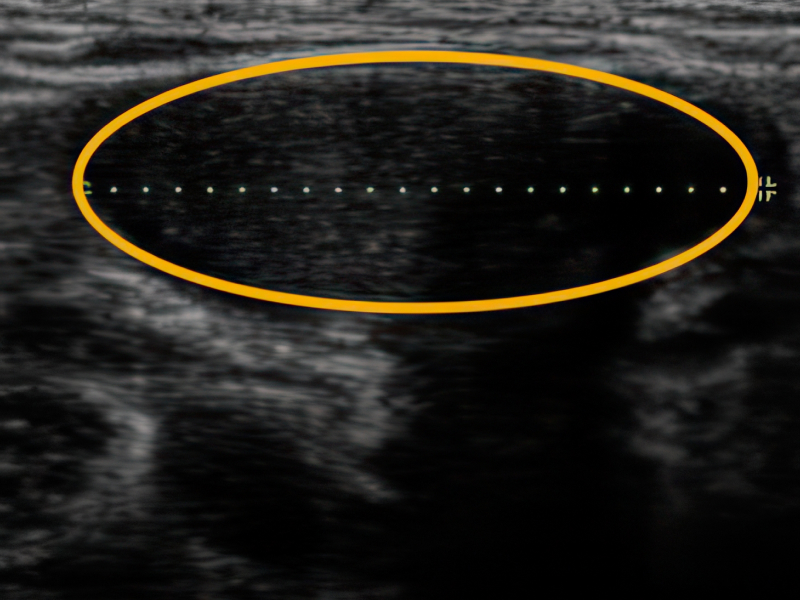

잠복고환 초음파